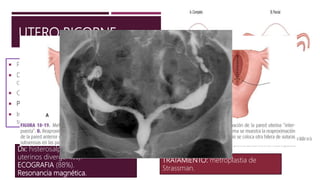

UTERO BICORNE

 Fusión incompleta de los conductos de Muller.

 Dos cavidades endometriales separadas,

comunicantes, único cuello.

 Culminación razonable de embarazos (60%).

 Parto prematuro.

 Incidencia de 66% de parto prematuro y menor

supervivencia fetal en el completo.

Dx: histerosalpingografia (cuernos

uterinos divergentes).

ECOGRAFIA (88%).

Resonancia magnética.

TRATAMIENTO: metroplastia de

Strassman.